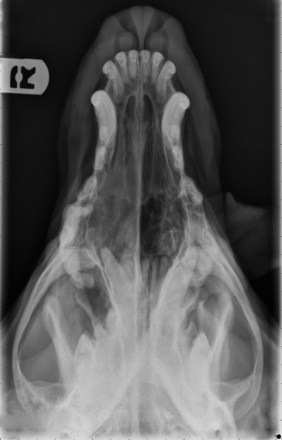

Radiography

Radiographic imaging or CT is always performed before rhinoscopy. Rhinoscopic iatrogenic hemorrhaging and irrigation fluid used during the procedure will distort tissue and create fluid densities that can influence the findings in any radiographic study. Nasal radiographs can be performed in most hospitals and, with practice, can be very useful in the localization and characterization of nasal and nasopharyngeal disease.5 Nasal radiographs require general anesthesia and special patient positioning. Most commonly performed are 30-degree beam-angled open-mouth ventrodorsal and straight lateral views. The open-mouth view provides a complete, symmetrical image of the nasal cavity without superimposition of the mandible. Tumors typically show asymmetrical opacities and turbinate destruction (Figure 19-6). Turbinate destruction is also seen with fungal rhinitis. The straight lateral view allows evaluation of the nasopharynx and frontal sinuses (Figure 19-7). Further study of the frontal sinuses is achieved with a rostrocaudal tangential view (Figure 19-8). This allows comparison of the left and right frontal sinuses as the cavities are superimposed on the lateral view. Dental films of the maxillary arcade are sometimes needed to rule out tooth root abscesses and oronasal fistulae. MRI and CT scans are becoming more commonly available and provide better detail of the nasal, nasopharyngeal, and sinus cavities and cranial vault anatomy compared with standard radiography.6,7 Advanced imaging via MRI and CT, although considered state of the art, assist in description and localization of diseased tissue but have not yet produced results specific enough to eliminate the need for rhinoscopy8,9 (Figures 19-9 through 19-11) (Table 19-1).

image

Figure 19-6 Canine open-mouth ventrodorsal view with right-sided destructive soft tissue mass; nasal osteosarcoma.